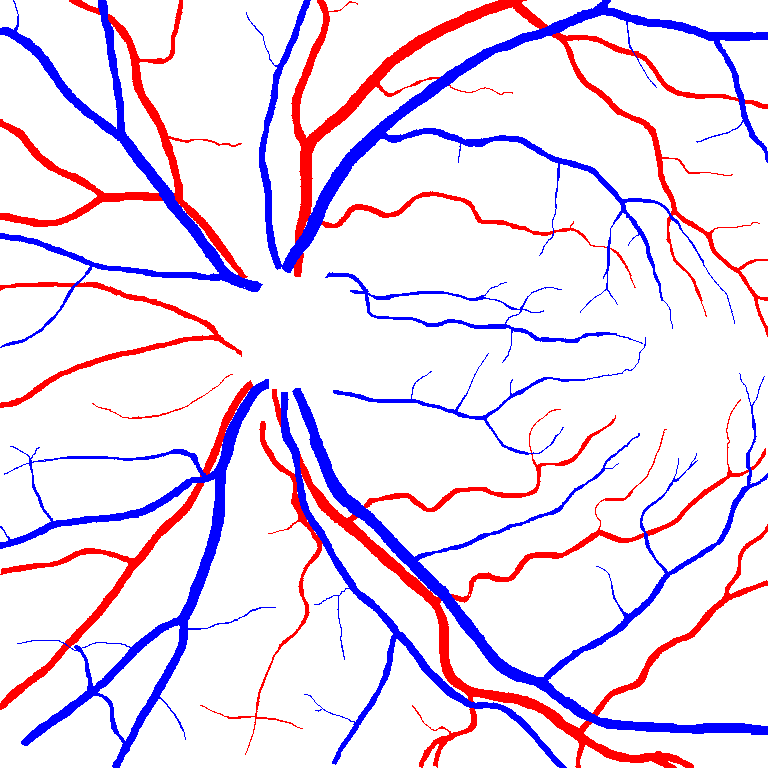

As reported in Table IV, we compared the SegRAVIR model against competing deep learning-based segmentation approaches on the RAVIR dataset. Evidently, SegRAVIR outperforms these methods as judged by all metrics for artery and vein classes with a healthy margin. In terms of Dice score, SegRAVIR outperforms CE-NET, IterNet and AG-Net by , and for artery segmentation and by , and for vein segmentation, respectively. Fig. 4 presents a qualitative comparison of the semantic segmentation outputs of SegRAVIR, CE-Net, and U-Net. Specifically, SegRAVIR yields more accurate vessel topology (i.e., thickness and orientation) segmentation with higher pixel-wise classification accuracy.

Table V presents quantitative performance benchmarks of SegRAVIR and other competing approaches for retinal artery and vein classification on the RITE dataset [11]. SegRAVIR outperforms previous state-of-the-art approaches in terms of accuracy, sensitivity, and specificity. Fig. 5 provides a qualitative comparison between segmentation outputs of SegRAVIR and the method of Hemelings et al. [40] on the RITE test set.